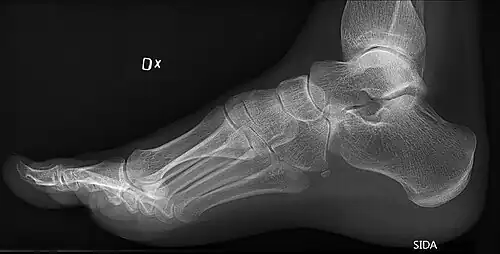

Foot with pes cavus (and os peroneum).